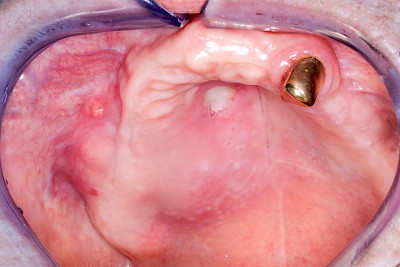

Schwellung ohne Eiter: kugelförmig

Demgegenüber entstehen Auftreibungen der Weichgewebe in Folge mechanischer Dauerreize (Reizfibrom) langsam über Wochen, Monate oder Jahre. Auch Gewohnheiten (Wangensaugen, Lippenbeißen) mit geringem Druck können als Dauerreiz in der Folge zu einer Wucherung der Weichgewebe führen. Fibrome werden nicht selten auch beobachtet in der Nähe einzelner fehlender Zähne – die Lippen oder Wangen beginnen dann, diesen Raum "aufzufüllen" (Vakatwucherung). Reizfibrome sind meist "kugelartig".